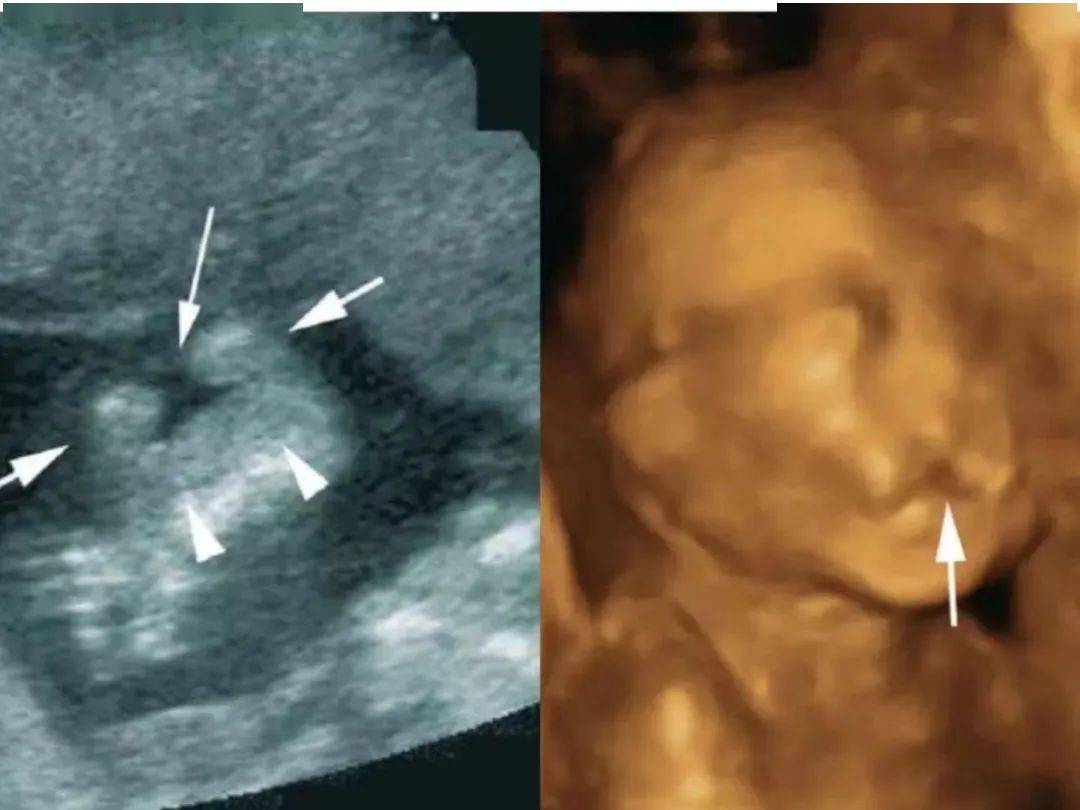

应用1:胎儿面部与唇腭裂的应用